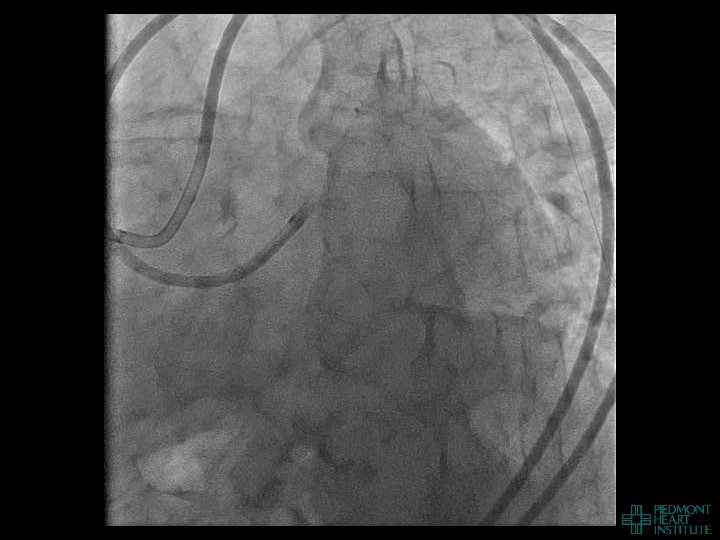

Case Example 2